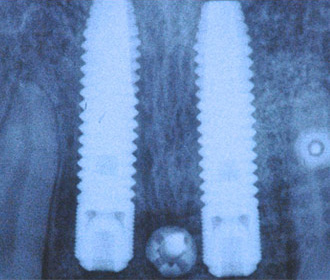

外傷による上顎左右11抜歯後即時インプラント+インビザライン矯正

インプラント治療時にはチタンメッシュ+人工骨による大掛かりな骨移植を行っている。

インプラント治療直後のレントゲン写真。

網目状のものがチタンメッシュ、ピンで骨に固定。 -